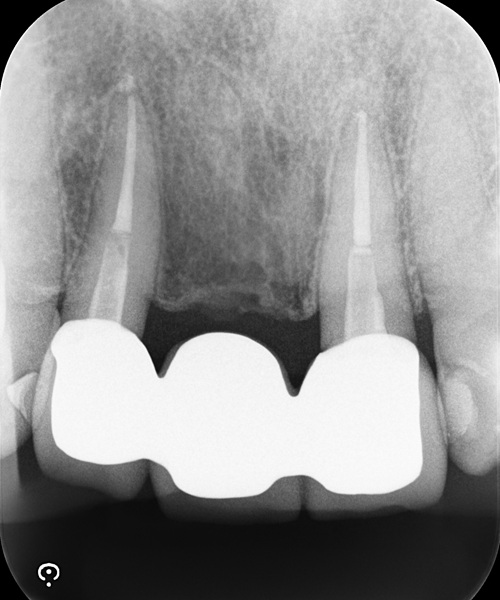

Case3

術前

術後

| 治療名 | 精密根管治療と前歯セラミッククラウンによる審美修復症例 |

|---|---|

| 治療説明 |

以前に治療された前歯の被せ物の見た目を気にされ、再治療をご希望されました。 審美性だけでなく、内部の根管治療まで丁寧に行うことで、将来的なトラブルのリスクを抑えた、長期的に安定した治療結果を目指しました。 |

| 治療回数・期間 | 4回 |

| 副作用とリスク | ・保険診療の銀歯と比べて費用が高額になります。 ・根管治療からクラウン装着までを含めると、治療期間が長くなる傾向があります。 |

| 料金(税込) | 精密根管治療:88,000円×2本 セラミッククラウン:132,000円×2本 合計:440,000円(税込) |